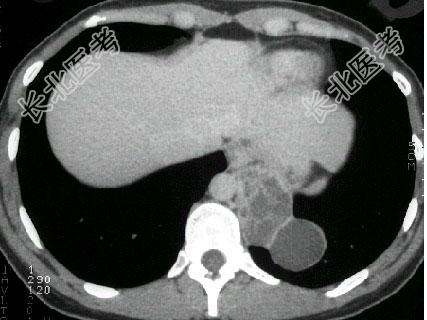

- 单项选择题男,18岁, 无明显症状, CT检查如图。最可能的诊断为 ( )

A、左下肺膈疝

B、左下肺肺隔离症

C、左下肺癌

D、神经纤维瘤

E、左下肺肺炎